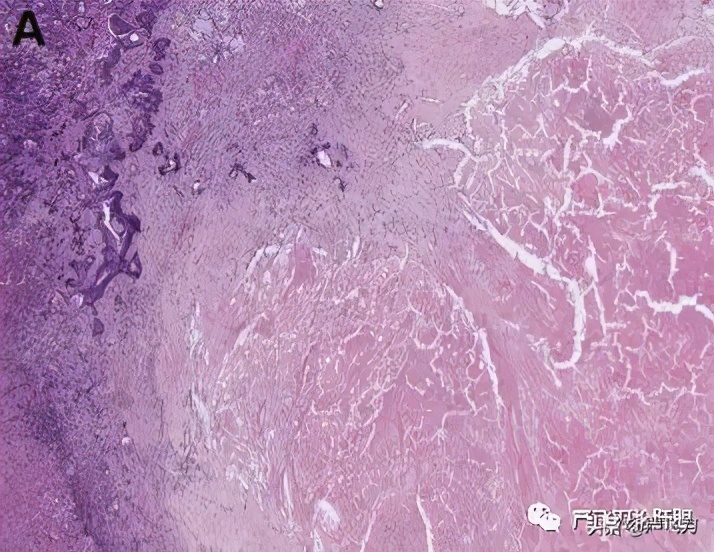

在患者接受贝伐单抗或西妥昔单抗治疗后,Stremitzer等人对不同的转移病灶组织进行了检测,他们发现,与西妥昔单抗相比,贝伐单抗联合化疗使得转移灶更多的坏死(图4),但更少的纤维化,并倾向于具有更高的组织学及放射学反应,和更长的无复发生存期。[7]

图4 坏死反应